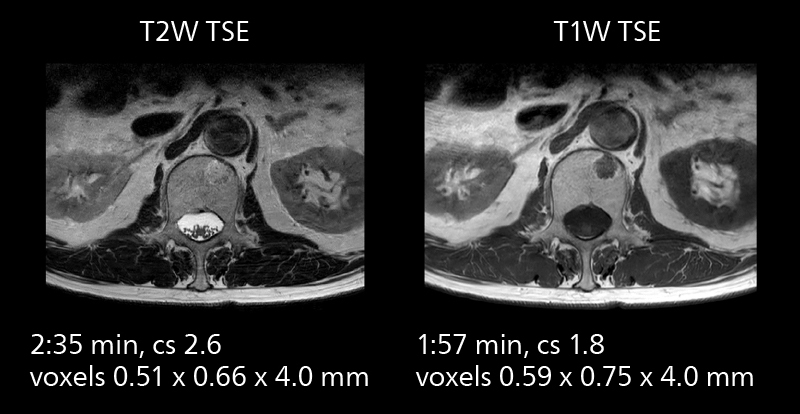

With SmartPath to Elition X the team can obtain excellent quality DWIBS imaging and reduce imaging time. Other sequences also fit in the examination slot. This case shows left paravertebral neurogenic tumor and Th10 vertebral hemangiomas.